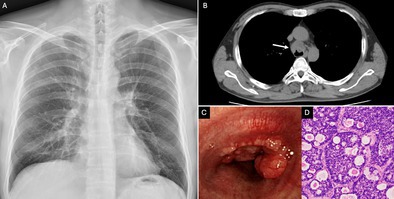

Tracheal tumours can develop as primary neoplasms or as extensions from adjacent organs such as the lungs or larynx. We present a case of a man diagnosed with adenoid cystic carcinoma of the trachea.

Abstract Image